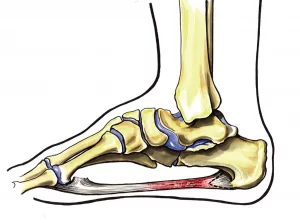

Ανατομία

Η πελματιαία απονεύρωση είναι ένας σύνδεσμος που βρίσκεται ακριβώς κάτω από το δέρμα στο πέλμα και συνδέει την πτέρνα με τα δάκτυλα και υποστηρίζει την καμάρα του ποδιού.